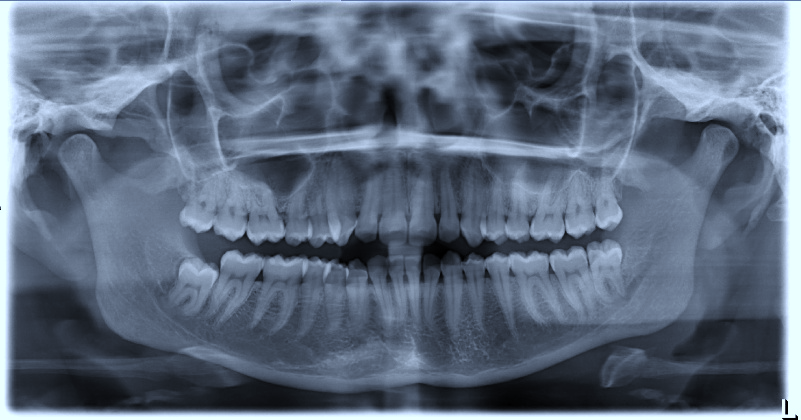

Tooth 4.8 is planned for extraction. Which radiographic findings suggest an increase in the degree of difficulty of the extraction?

13. (Select ONE OR MORE correct answers.)

Tooth 1.8 is planned for surgical extraction. Which radiographic findings suggest an increase in the degree of difficulty of the extraction?

Tooth 2.8 is planned for surgical extraction. Which radiographic findings suggest an increase in the degree of difficulty of the extraction?